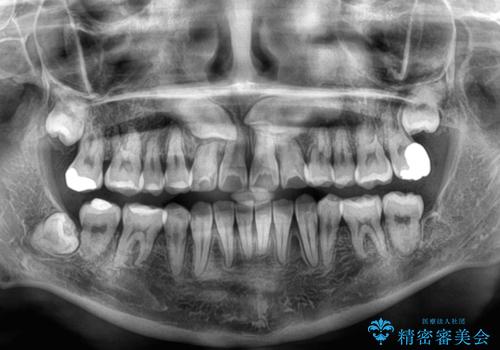

下顎は第二小臼歯を抜歯したため、治療期間が長期化すると思われましたが、大臼歯が後方に傾斜していたため、容易にスペースを閉じることができ、2年強で治療を終えることができました。